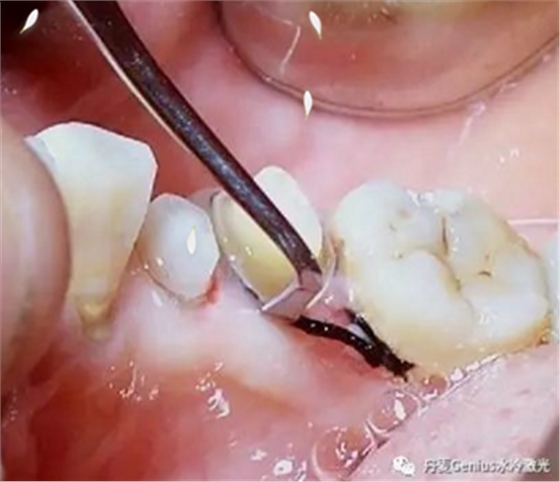

排齦/種植牙維護(hù)

排齦-排齦操作前3分鐘,表麻涂抹于牙齦上,有效緩解剝離游離齦過程中產(chǎn)生的疼痛

種植牙維護(hù)-將凝膠涂抹局部,維護(hù)過程中,緩解疼痛。術(shù)后出現(xiàn)疼痛也可以直接涂抹,快速止痛。